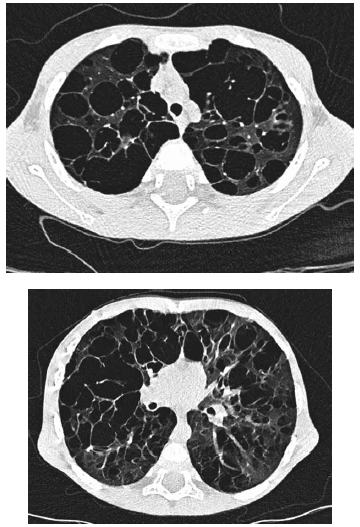

Considere as imagens e a seguinte descrição: menino, com cinco anos de idade, com piora lenta e progressiva de falta de ar há mais de um ano e piorando no último mês, impossibilitando-o de brincar.

O diagnóstico mais provável é: